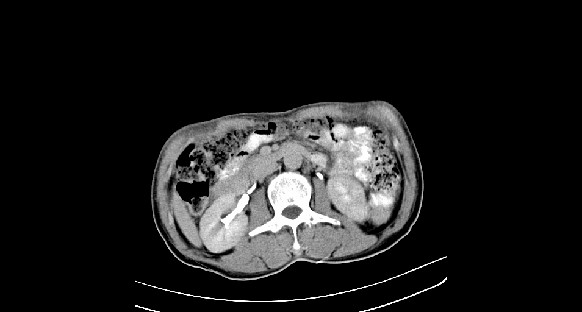

男性,70岁,体检b超发现左肾占位,请各位战友发表一下观点

左肾有两个病灶,且较大的病灶内可见点状钙化灶,增强扫描边缘也是呈渐进性强化,中央部分未见明显强化

考虑左肾脏错构瘤可能,不除外肾癌。

肾癌较肾aml可能大,建议mri,若t2明显高信号者则肾癌基本诊断明确。